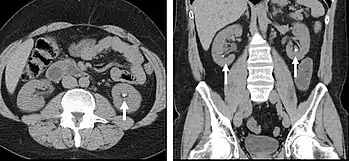

A CT scan image showing a ruptured abdominal aortic aneurysm.

FIGURE 3. Axial (left) and coronal (right) CT angiography images of the abdominal aorta evaluating for aortic aneurysm.

CT angiography (CTA) is highly effective for evaluation of the arterial system, and has largely replaced conventional angiography due to the lower risk profile and ability to survey the entire abdomen. Images are acquired after a rapid bolus of intravenous contrast material (3-7 cc/s) during the arterial phase (15–35 seconds after injection) when the concentration of contrast material in the arterial system is high (figures 3). Images are usually acquired using narrow collimation (<1 mm) and can be retrospectively reconstructed using dedicated 3-dimensional workstations and software. CTA is commonly used in the head and chest in the evaluation of pulmonary emboli, aneurysms, vascular malformations, dissection, bleeding and ischemia. Indications for early arterial phase imaging include: evaluation of aneurysms or dissections (cerebral, aortic, etc.), hepatic, splanchnic or renal arterial anatomy, and arterial imaging in liver or kidney transplantation. Single phase arterial imaging is often used in the evaluation of trauma patients either a complete chest/abdomen/pelvis examination with arterial phase imaging of the chest and portal venous phase imaging of the abdomen/pelvis or just a portal venous phase of abdomen and pelvis depending on the mechanism and severity of the trauma. CTA is also commonly performed in the abdomen and pelvis for evaluating vascular malformations and in the evaluation of bleeding. Mesenteric ischemia can also be evaluated using CT angiography. CTA of the abdomen and pelvis is often performed in combination with a CTA for evaluating the extremity vasculature.